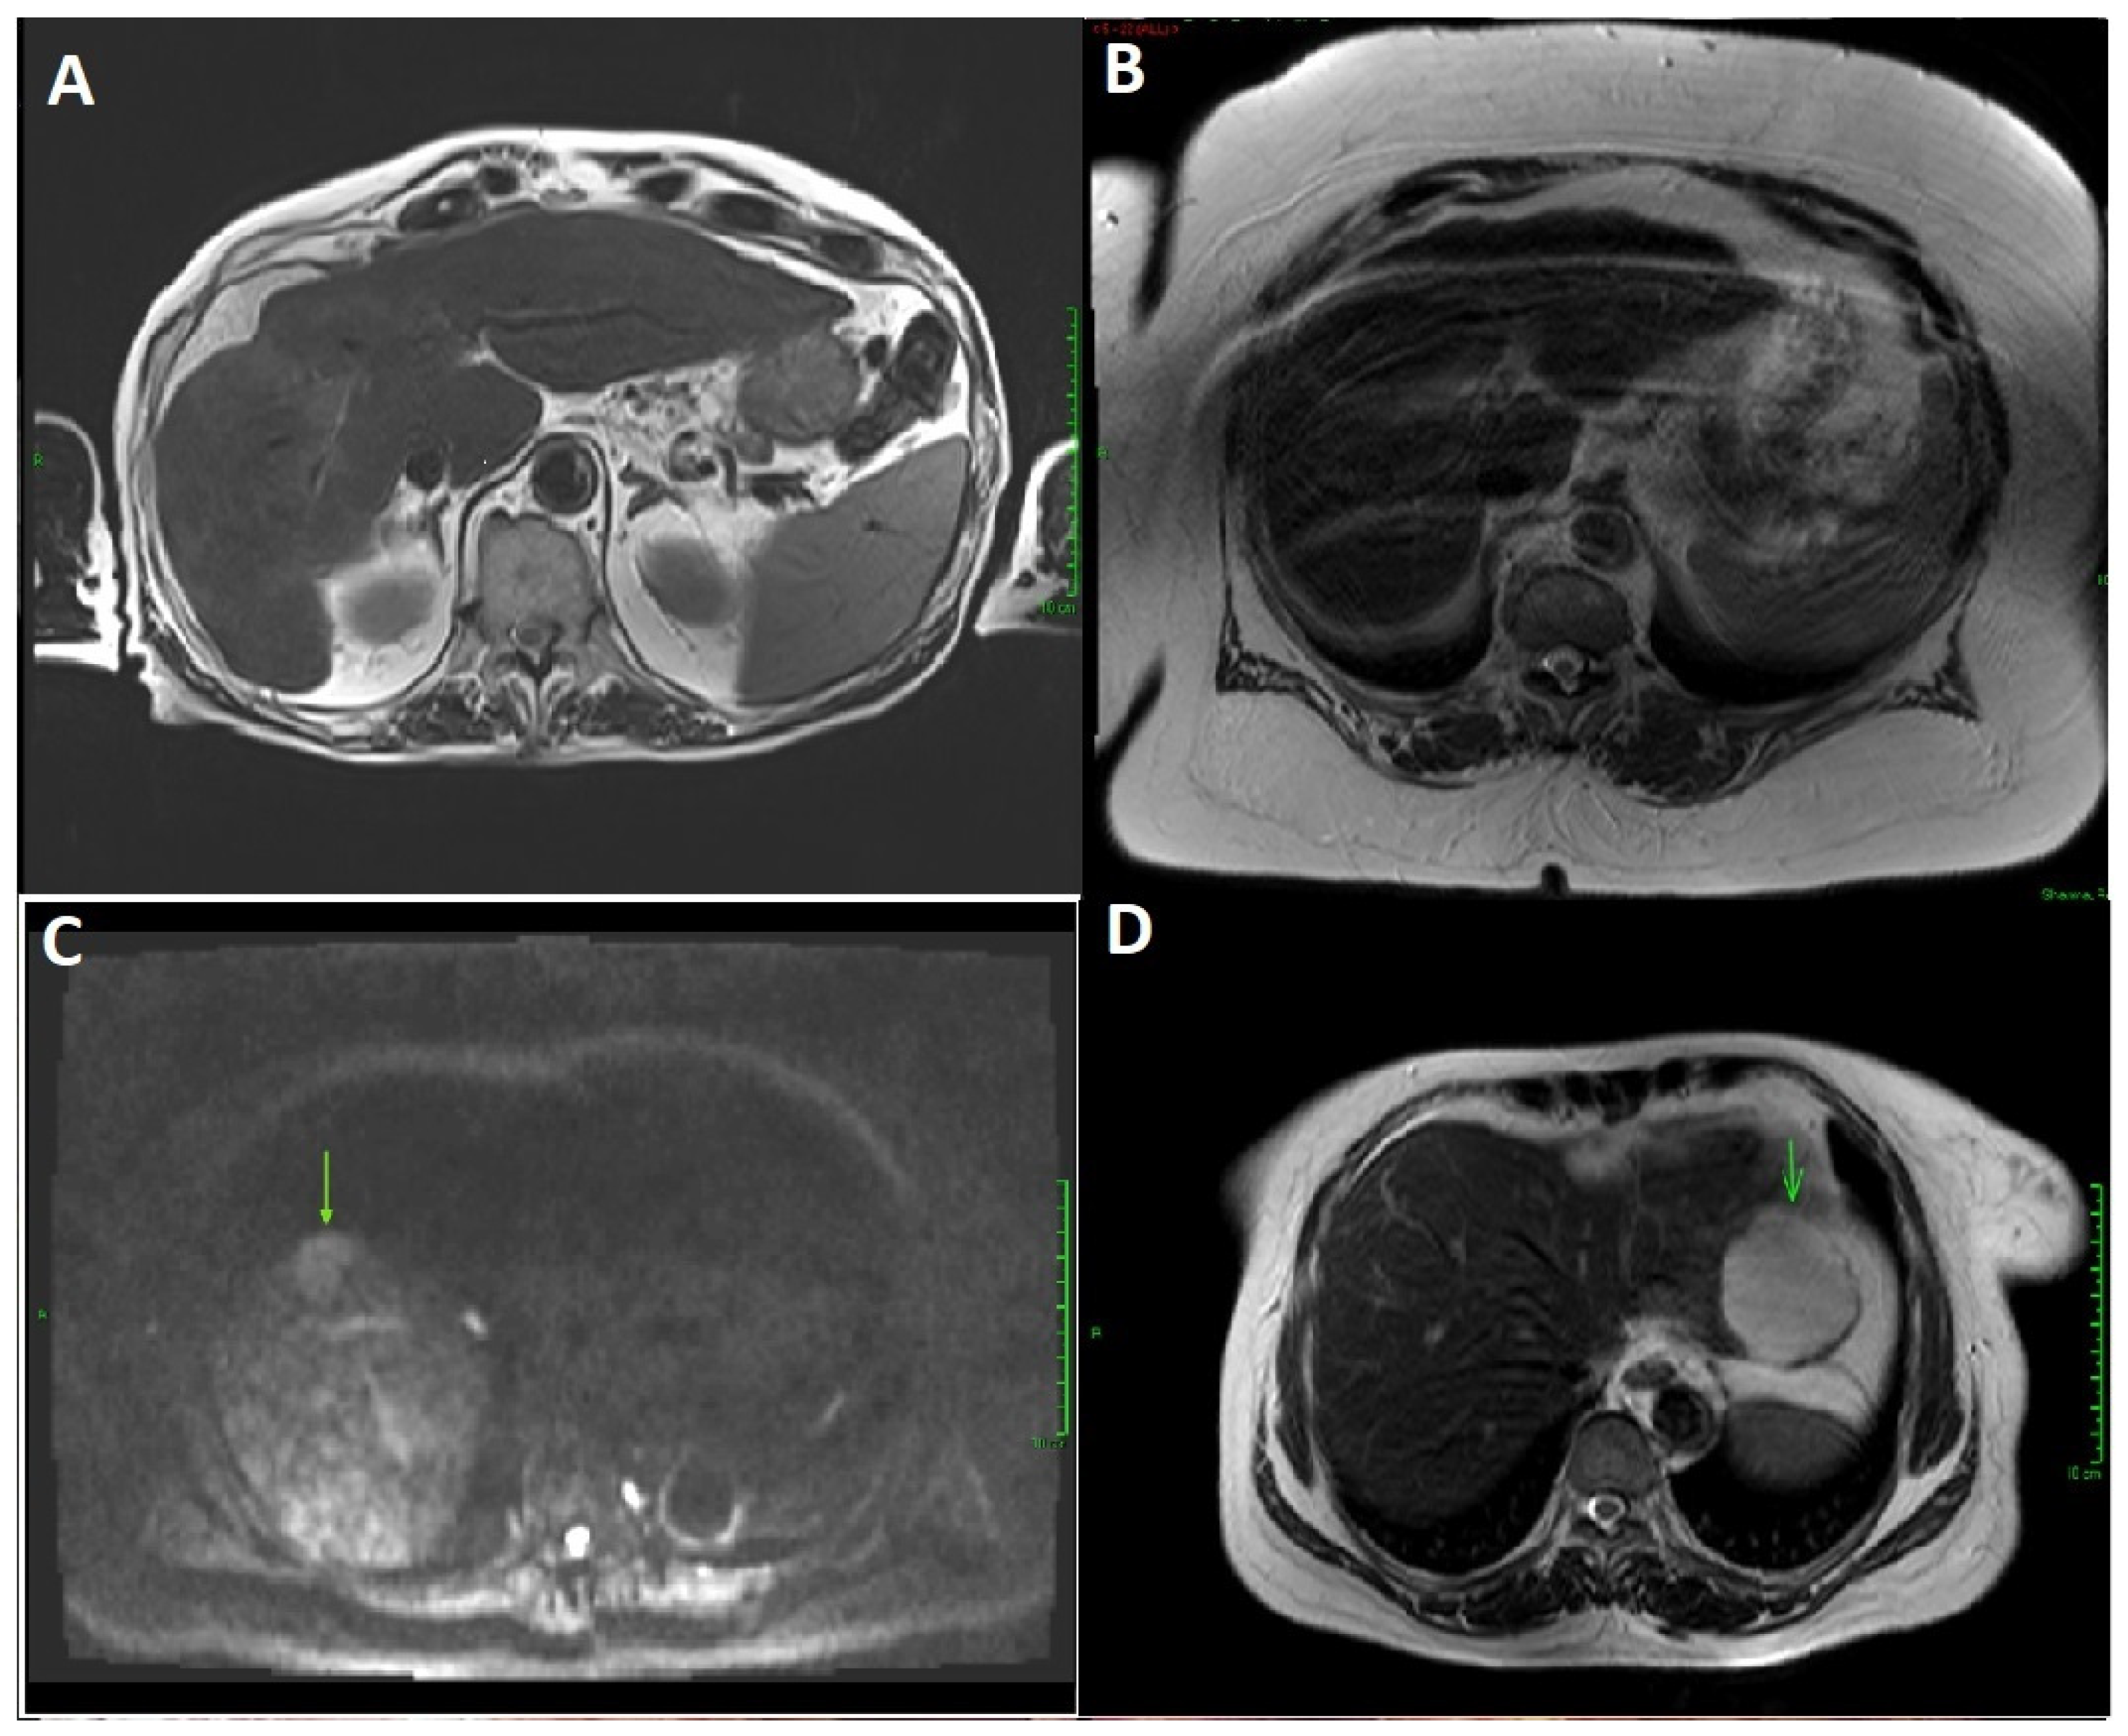

Figure 3.

Abbreviated MRI images from study participants. (A). Satisfactory quality abbreviated MRI in a patient with ArLD cirrhosis, with no lesion detected. (B). Insufficient quality abbreviated MRI due to breathing artefact in patient with body mass index > 55. (C). Hepatocellular carcinoma (arrow) in a patient with cirrhosis, with no lesion detected on surveillance ultrasound. (D). Haemangioma (arrow) in a patient, with no lesion detected on ultrasound.

Six patients (20%) had a hepatic abnormality detected with aMRI and underwent further contrast imaging for the characterisation of hepatic lesions. Following contrast MRI, one lesion was confirmed as HCC (Figure 3C), one lesion as haemangioma (Figure 3D), and four suspected lesions were not seen on contrast imaging or were too small to be of clinical significance.